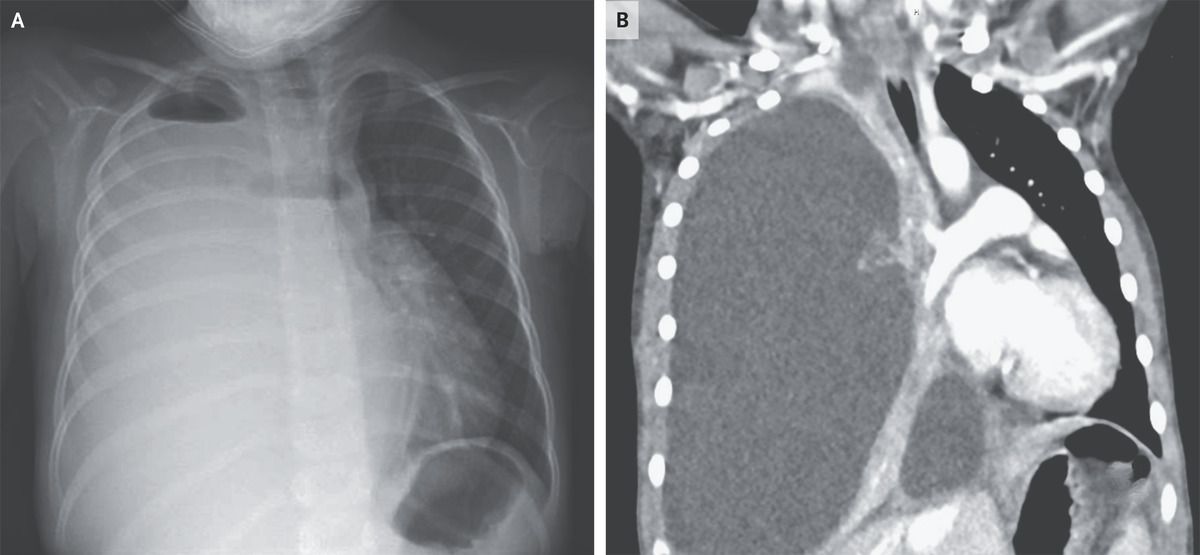

A 4-year-old girl was brought to the emergency department with a 4-day history of fever, cough, and lethargy. She was up to date with all childhood vaccinations. Three weeks earlier, she had had a presumed viral respiratory tract infection with fever and cough; testing for severe acute respiratory syndrome coronavirus 2 had been negative at that time. On arrival during the current presentation, she had a heart rate of 136 beats per minute, a respiratory rate of 32 breaths per minute, and an oxygen saturation of 92% while she was breathing ambient air. Auscultation of the lungs was notable for the absence of breath sounds on the right side and diminished breath sounds on the left. Laboratory studies showed a leukocyte count of 25,300 per cubic millimeter (reference range, 5000 to 15,500) with 88% neutrophils. Chest radiography revealed opacification of the right hemithorax with apical air–fluid levels, indicating the presence of a hydropneumothorax (Panel A). Findings on computed tomography of the chest included right lung collapse due to massive effusion and leftward mediastinal shift (Panel B). The left lung parenchyma appeared normal, without abscesses or cysts. The patient underwent chest-tube placement, and 1 liter of cloudy fluid was evacuated. Pleural fluid cultures grew Streptococcus pneumoniae. Pneumococcus remains an important cause of postviral pneumonia and empyema, even in fully vaccinated children. The patient received 14 days of treatment with ceftriaxone. At a 3-month follow-up visit, she had recovered fully, and a repeat chest radiograph was normal.